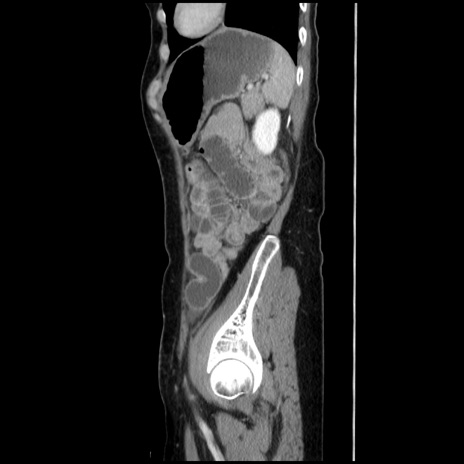

冠状断像

【症例】40歳代 女性

【主訴】上腹部痛、嘔気・嘔吐

【現病歴】約9時間前頃から急に上腹部痛、嘔気、嘔吐が出現。改善しないため救急要請。

【既往歴】子宮頚癌(広汎子宮全摘術、放射線療法)、腸閉塞

【身体所見】腹部:平坦、軟、腸雑音亢進、上腹部を中心に腹部全体に圧痛あり。

【データ】WBC 8400、CRP 0.03